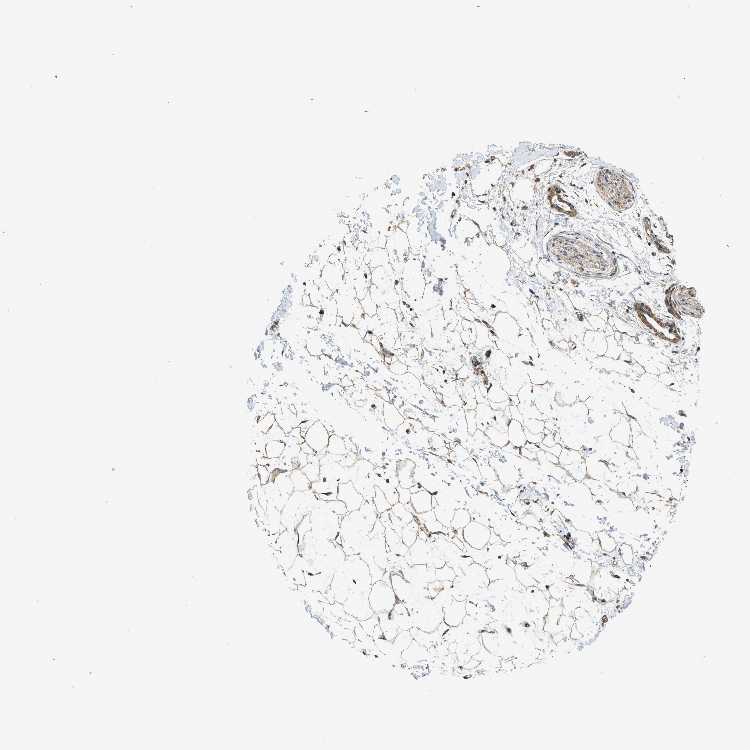

ADIPOSE TISSUE - Antibody stainingi

Antibody staining in the annotated cell types in the current human tissue is reported as not detected, low, medium, or high, based on conventional immunohistochemistry profiling in selected tissues. This score is based on the combination of the staining intensity and fraction of stained cells.

Each image is clickable and will lead to virtual microscopy that enables deeper exploration of all samples and also displays staining intensity scores, fraction scores and subcellular localization as well as patient and tissue information for each sample.

Antibody CAB017716

Adipocytes Medium